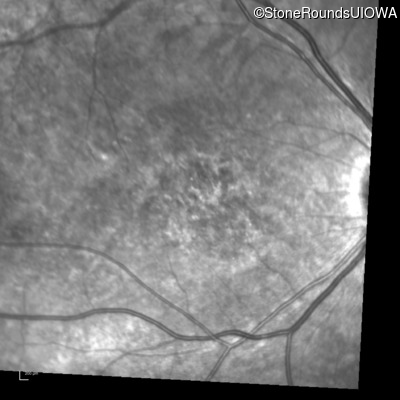

Infrared Fundus Photograph - Left - 10/300 sc

Exemplar